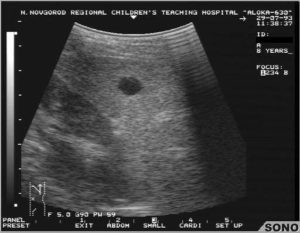

Обнаружить небольшие кисты у новорожденных помочь может только УЗИ – пальпация образование не выявит, симптомов может не быть совсем, а ребенок не в состоянии сказать, где именно ощущается дискомфорт (даже если он есть).

Подобную патологию можно обнаружить только при проведении планового УЗИ малыша.

Лечебная терапия, если диагностирована киста селезенки у ребенка, назначается только после проведения комплексной диагностики. Диагноз ставится на основании данных анамнеза, по результатам УЗИ.

Чаще всего выявление кисты в селезенке происходит случайно, при прохождении пациентом УЗИ в ходе диагностики других заболеваний

- ультразвуковое исследование органа внутренней кисты селезенки. УЗИ является основным способом уточнения диагноза.

Во время процедуры выявляют разновидность кисты, ее размер, место расположения на внутреннем органе;